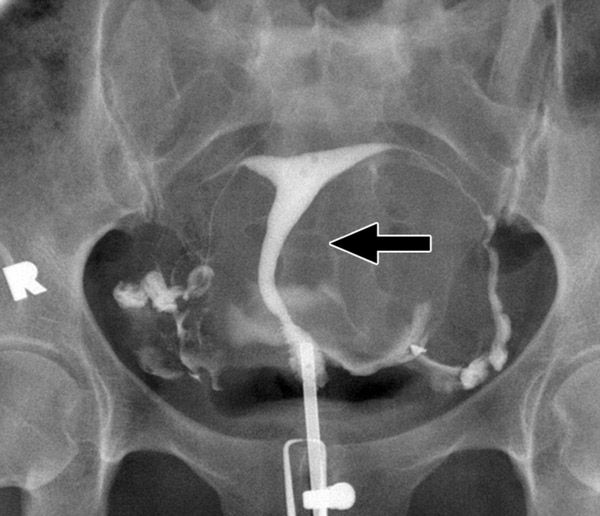

УЗИ проходимости маточных труб – это безопасная и неинвазивная процедура, которая может помочь выявить причины бесплодия и помочь врачу разработать план лечения. Но не всегда способно однозначно подтвердить непроходимость маточных труб. Для более точной диагностики может потребоваться проведение других процедур, таких как гистеросальпингография (ГСГ) или лапароскопия. ГСГ - это процедура рентгеновской диагностики, которая позволяет непосредственно визуализировать проходимость маточных труб с использованием контрастного вещества.